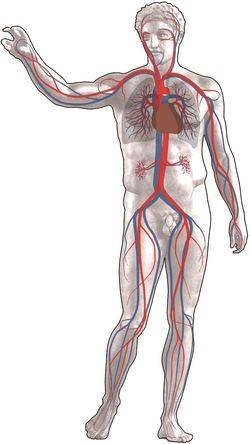

Grote bloedsomloop

Arteriën (in het rood) voeren zuurstofrijk bloed van het hart naar de weefsels, de venen (blauw) voeren zuurstofarm bloed terug van de weefsels naar het hart.

Kleine bloedsomloop

Longarteriën voeren zuurstofarm bloed naar de longen, de longvenen voeren het zuurstofrijke bloed van de longen naar het hart.